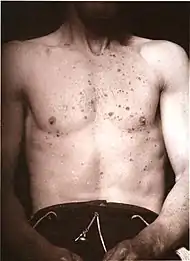

| Allergic/contact dermatitis or atopic dermatitis | As above. Eosinophils may be present in the dermis and epidermis (eosinophilic spongiosis).[2] |  Allergic dermatitis Allergic dermatitis |

.jpg.webp) Atopic dermatitis Atopic dermatitis | ||